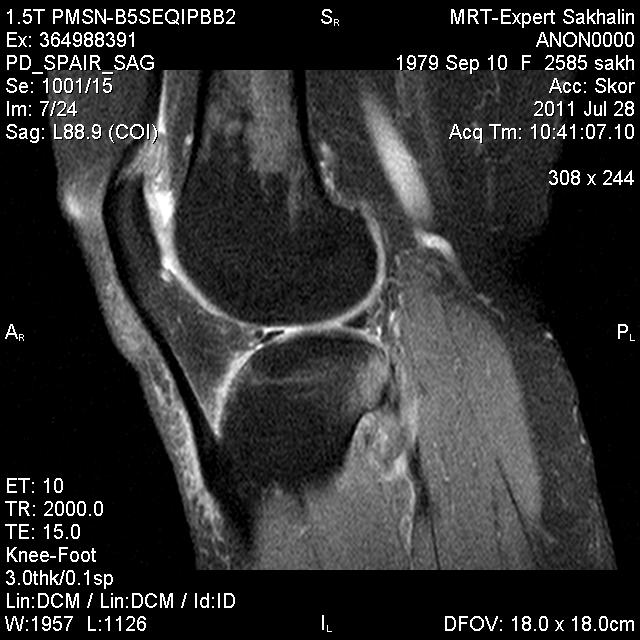

Коленный сустав

Подглядела случай у коллеги.

Что это может быть?

P.S. В костях - это, скорее всего, резидуальный красный костный мозг.

участки гемопоэтического костного мозга